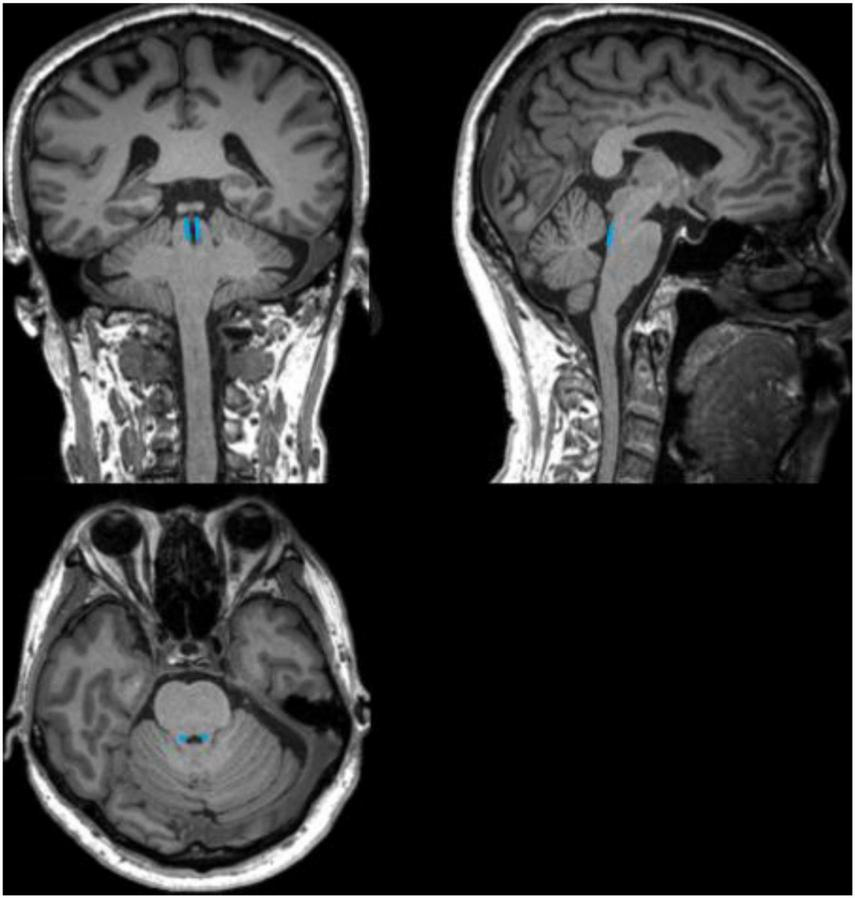

FIGURE 3

Schematic diagram of the anatomical location of the locus coeruleus (LC). The schematic diagram shows coronal, sagittal, and axial 3D-T1WI images from a 71-year-old healthy control, with the anatomical location of the LC outlined in blue.